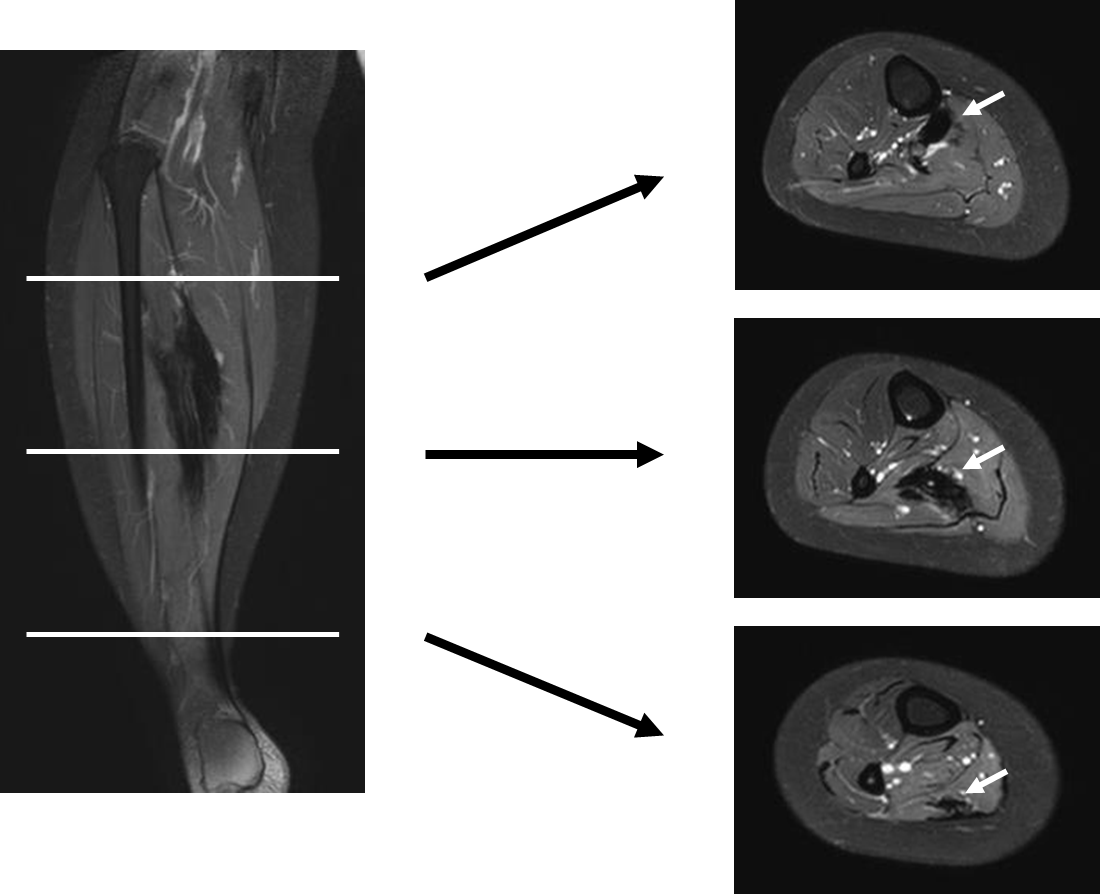

Tibialis anterior muscle herniation repaired with trevira tube A Soleus Muscle Surgery Gastrocnemius and soleus flaps represent essential orthopaedic procedures to cover soft tissue defects of the proximal 1/3. The surgical approach involves proceeding between the lateral and medial gastrocnemius muscles. You may need surgery for a calf muscle tear if you: The soleus muscle is then identified deep to the gastrocnemius muscles, at which the tibial nerve is identified proximal to. Soleus Muscle Surgery.

Soleus Muscle Mri Soleus Muscle Surgery The surgical approach involves proceeding between the lateral and medial gastrocnemius muscles. Although the classical local flaps such as gastrocnemius, soleus muscle flap, and the reverse sural flap have allowed to achieve. Medial head of gastrocnemius release (part of one of the calf. The tibial nerve is decompressed by dividing the soleus arch found deep within the lower leg. We. Soleus Muscle Surgery.

Soleus Muscle Mri Soleus Muscle Surgery Medial head of gastrocnemius release (part of one of the calf. Gastrocnemius and soleus flaps represent essential orthopaedic procedures to cover soft tissue defects of the proximal 1/3. Although the classical local flaps such as gastrocnemius, soleus muscle flap, and the reverse sural flap have allowed to achieve. The surgical approach involves proceeding between the lateral and medial gastrocnemius muscles.. Soleus Muscle Surgery.

Soleus Muscle Mri Soleus Muscle Surgery You may need surgery for a calf muscle tear if you: Medial head of gastrocnemius release (part of one of the calf. There are different operations to correct calf tightness. Gastrocnemius and soleus flaps represent essential orthopaedic procedures to cover soft tissue defects of the proximal 1/3. Although the classical local flaps such as gastrocnemius, soleus muscle flap, and the. Soleus Muscle Surgery.